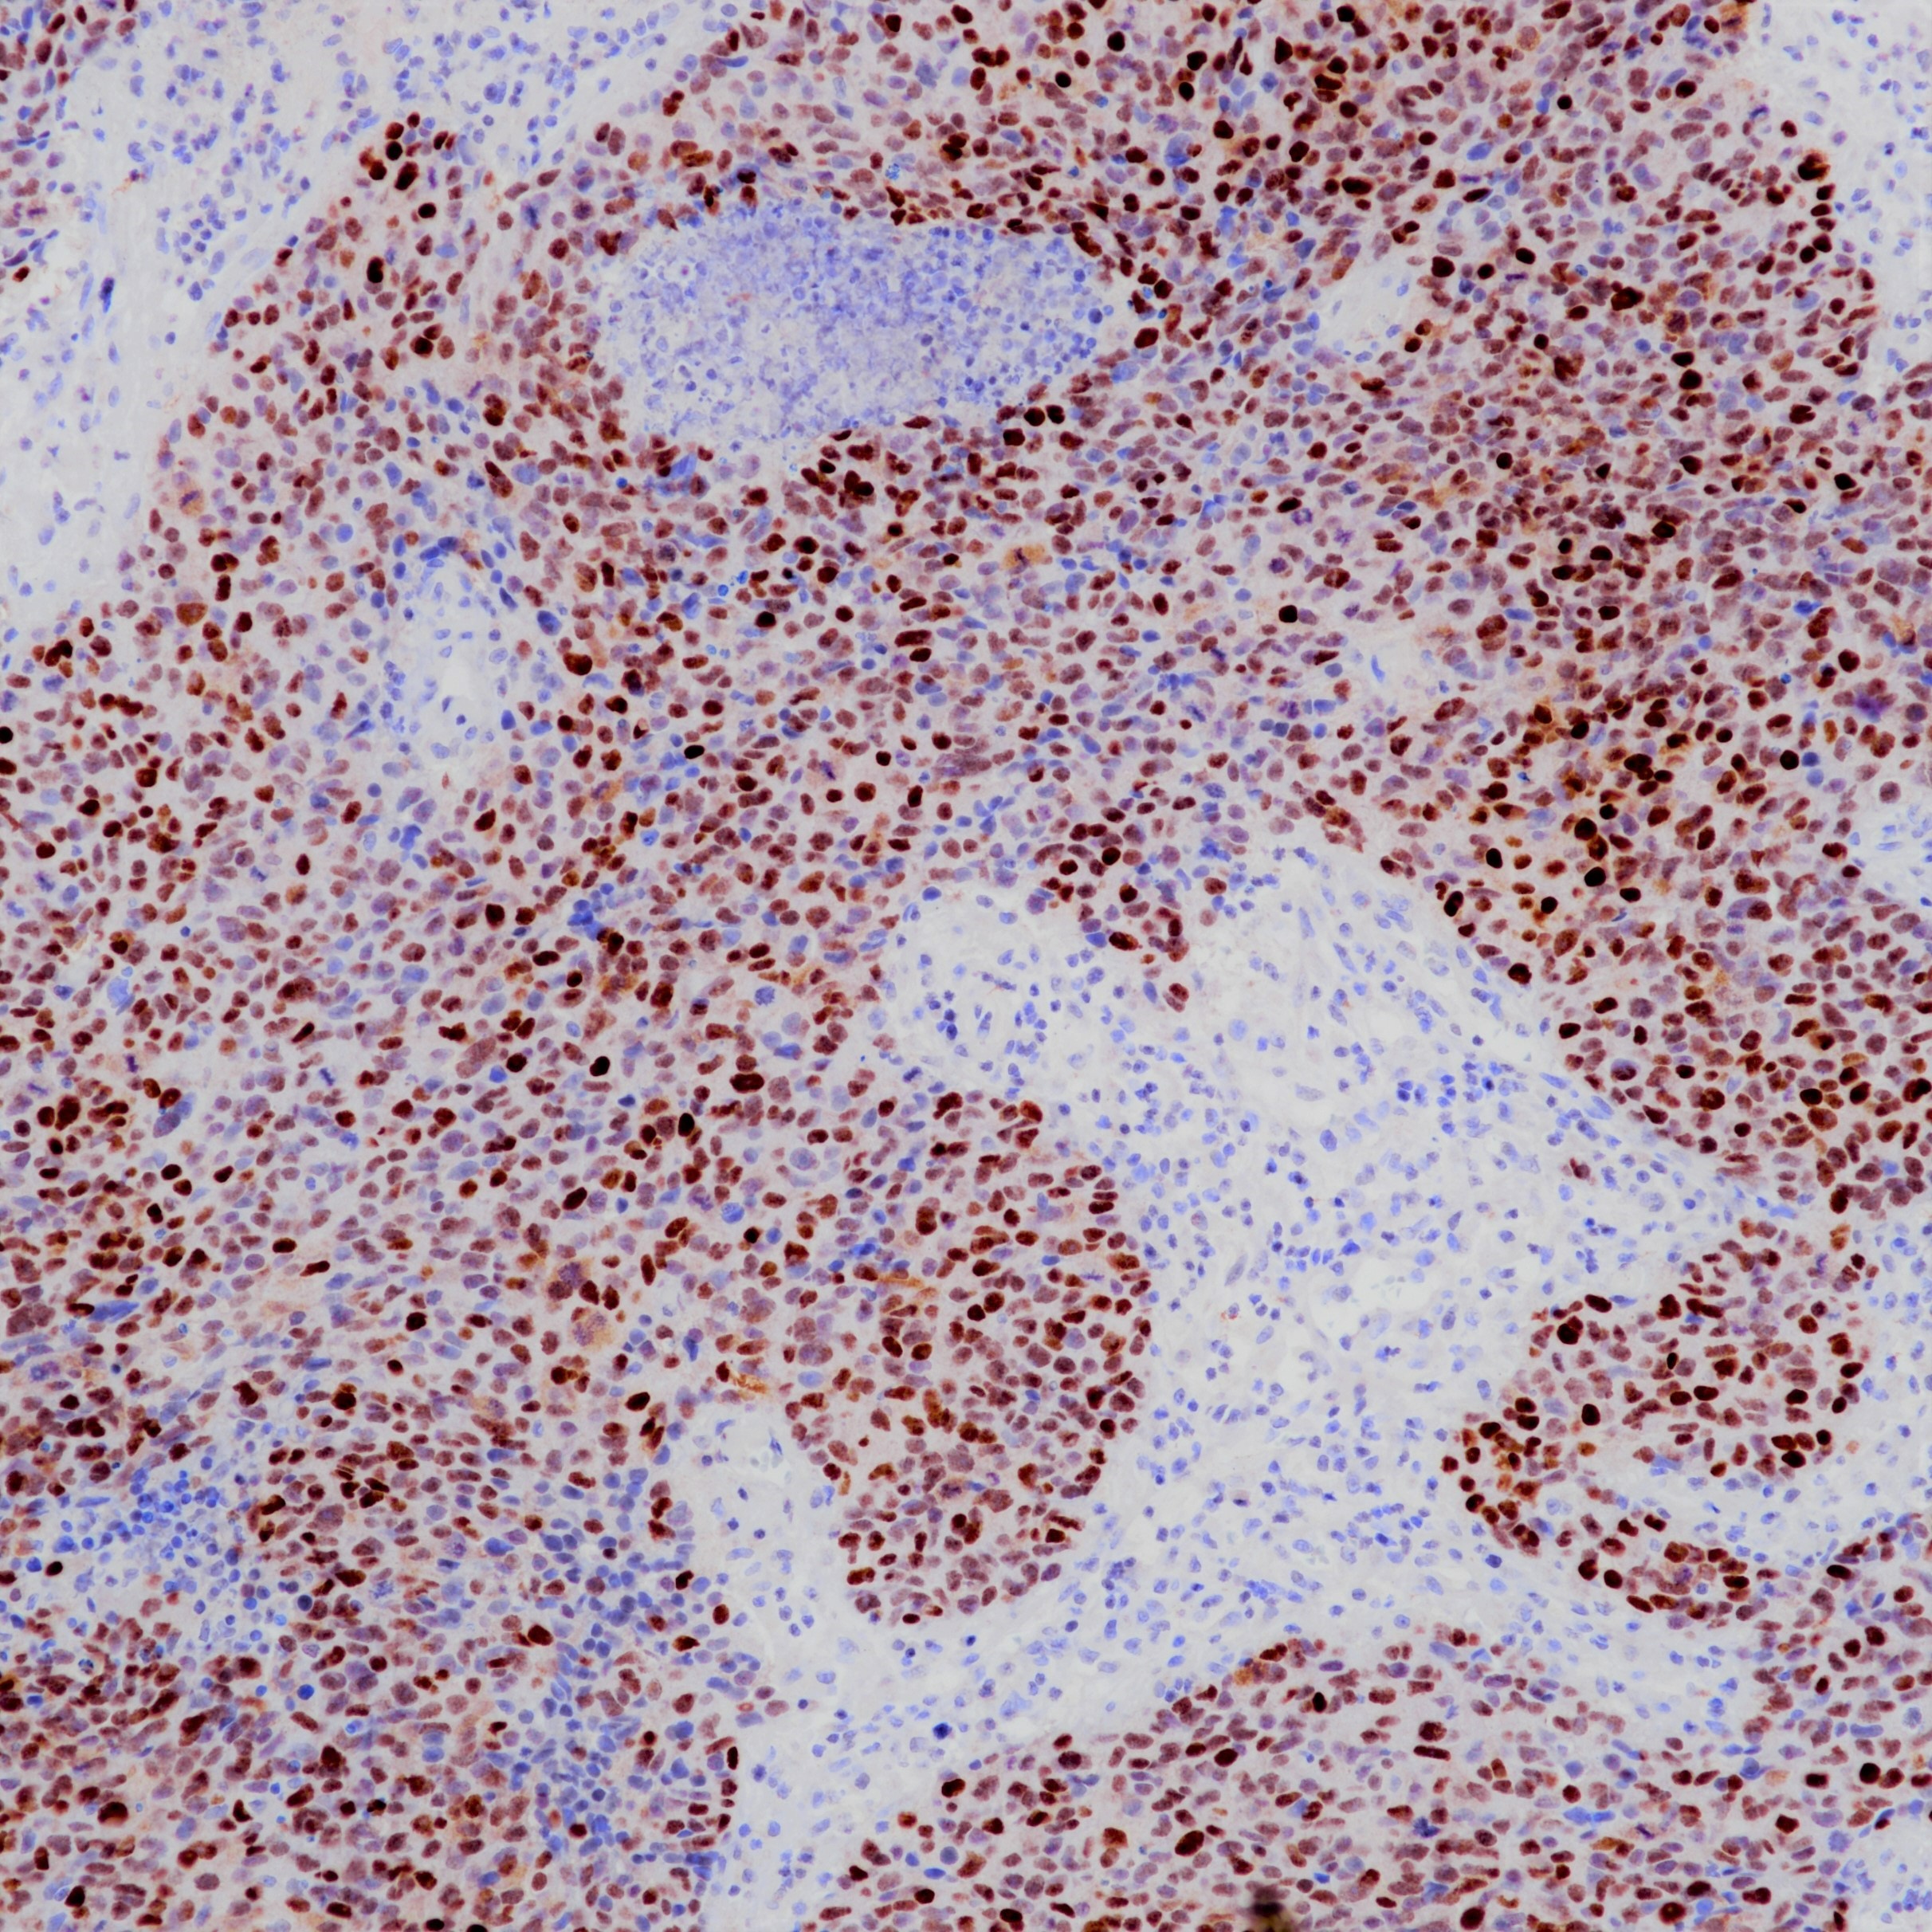

1. Butler M, Pongor L, Su YT, Xi L, Raffeld M, Quezado M, Trepel J,Aldape K, Pommier Y, Wu J. MGMT Status as a Clinical Biomarker in Glioblastoma. Trends Cancer. 2020 May;6(5):380-391.

2. Rao AM, Quddusi A, Shamim MS. The significance of MGMT methylation in Glioblastoma Multiforme prognosis. J Pak Med Assoc. 2018 Jul;68(7):1137-1139.